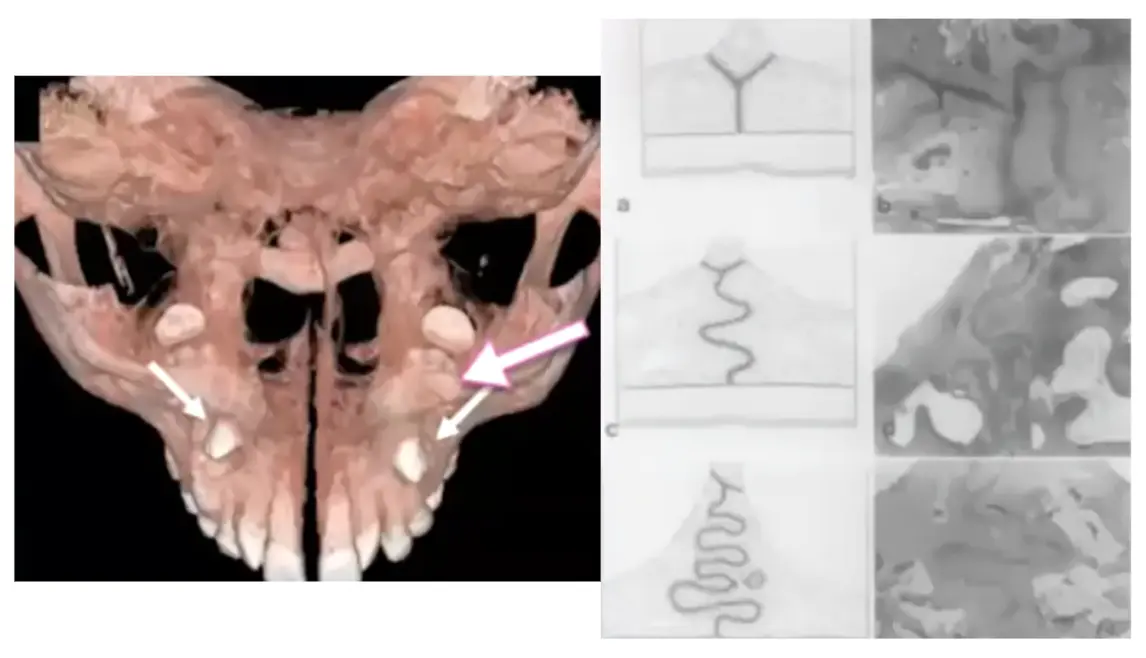

Imaging and diagram reference of the midpalatal suture Illustration of the midpalatal suture along the palate

Why the Midpalatal Suture Matters in Adults

The midpalatal suture is the seam that joins the right and left halves of the upper jaw and plays a major role in how the upper arch responds to expansion. In adults, this area is usually more interlocked, denser, and more resistant than it is in younger patients, which means conventional tooth-borne expansion may produce more dental tipping and less true skeletal widening. Because adult skeletal anatomy is more mature, selected cases may require MARPE to direct force more effectively toward the suture and supporting bone, improving the potential for meaningful transverse correction and more stable width development.